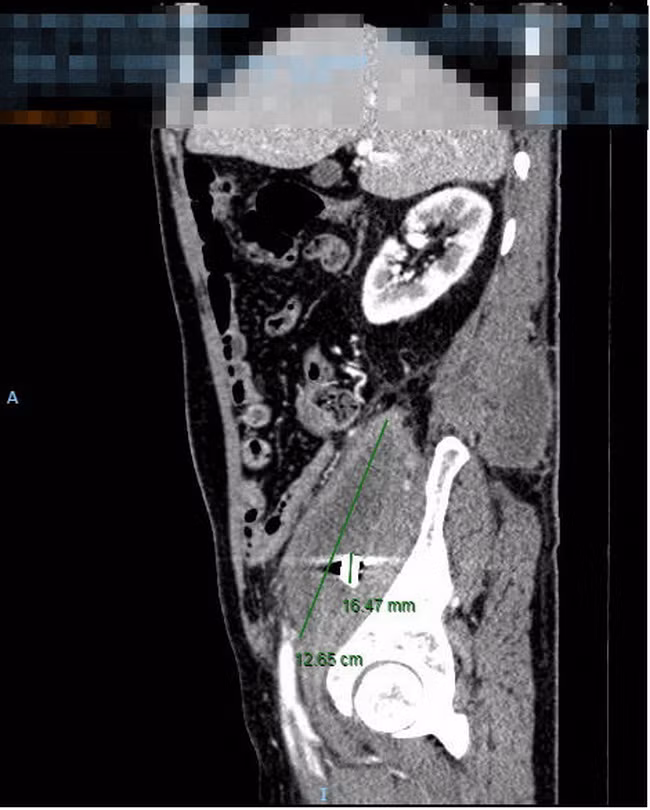

| Hình chụp CT. |

Qua thăm khám toàn diện, chụp cắt lớp điện toán vùng bụng, các bác sĩ phát hiện có một ổ áp xe to tại vùng cơ thắt lưng chậu phải, ổ áp xe đã lan ra sau lưng.

Sâu bên trong ổ áp xe có ghi nhận từ hình ảnh nghi ngờ của mảnh kim loại, tương ứng với mảnh đạn quá khứ trong người chú K. Kết quả xét nghiệm máu cho thấy, tình trạng bạch cầu máu của chú K có tăng cao, dấu hiệu nhiễm trùng nặng.

Với chẩn đoán áp xe lớn cơ thắt lưng chậu bên phải nghi do mảnh đạn, các bác sĩ khoa Ngoại Tiêu hóa BV ĐHYD đã chỉ định mổ cấp cứu cho chú K.